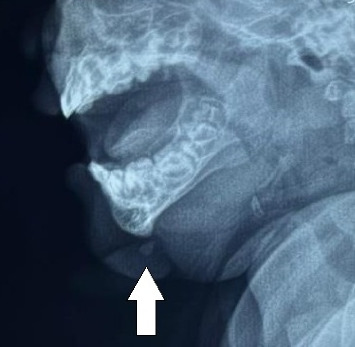

Background: Teratoma is a tumor usually consisting of tissues derived from multiple germ layers. A congenital teratoma occurring in the region of the head and neck is rare with barely 10 reports in the global literature since 1996. Of further rarity is its mandibular location. This probably represents the first report of its kind in the world in addition to being the first one to be reported from Nepal. Case Presentation: We report a case of an 11-month-old infant with a congenital appendage over the side of the chin that was treated with surgical excision and histologically confirmed as mature teratoma. Conclusion: Congenital facial teratoma in the mandibular location is a rare event. A principle combining appropriate surgical technique and correct oncological principles keeping esthetic appearance in mind is necessary for the best outcome.